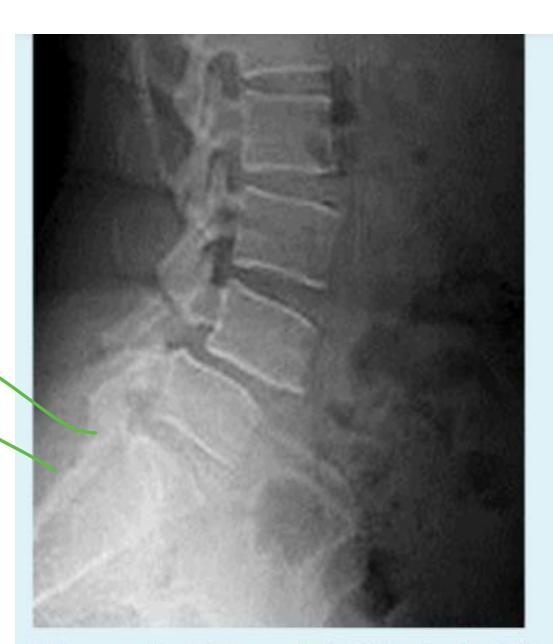

Lady came to the clinic complaining of long standing low back pain

Description Lateral x-ray of lumbar spine showing a fracture in the pedicle & slipped L4 over L5

Diagnosis: Spondylolisthesis

Diagnosis: Spondylolisthesis Next step? Oblique view - to see Scotty dog

Anterior displacement of L4 over L5, pars interarticularis disruption, osteopenia

Nerve compression may cause inability to control bowel and bladder sphincter, chronic pain and numbness